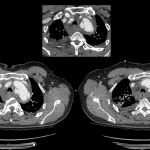

Age: 63

Sex: Male

Indication: Trauma

Findings

- Widening of the superior mediastinum, which also has an abnormal convex contour

- Acute right posterior third through ninth fractures

- Patchy right infrahilar opacity

- No pleural effusion or pneumothorax

Diagnosis

- Acute aortic injury

Widening of the superior mediastinum, which also has an abnormal convex contour. Findings are concerning for hematoma or aortic injury in the context of trauma. Recommend chest CTA for further evaluation.

Patchy right infrahilar opacity may reflect atelectasis, contusion, or aspiration in the setting of trauma.

Acute right posterior third through ninth rib fractures. No pneumothorax or pleural fluid collection.